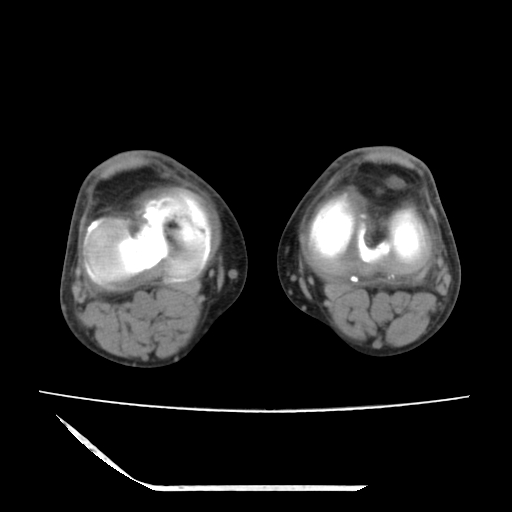

标题: CT13225:老年男性,左膝关节疼痛数月;请各位老师讨论。 [打印本页]

标题: CT13225:老年男性,左膝关节疼痛数月;请各位老师讨论。

骨质增生,骨性关节面硬化,关节积液,考虑退行性骨关节病

关节腔内少量积液,关节面退变。

双膝退变

骨质增生,骨性关节面硬化,关节间隙失常,关节积液,考虑退行性骨关节病.

骨质增生,骨性关节面硬化,关节积液,考虑退行性骨关节病。

这是由于两侧的肌肉不对称所致,加上扫描的平面也有些差异。请看示意图:

这个病例诊断:退行性骨关节炎